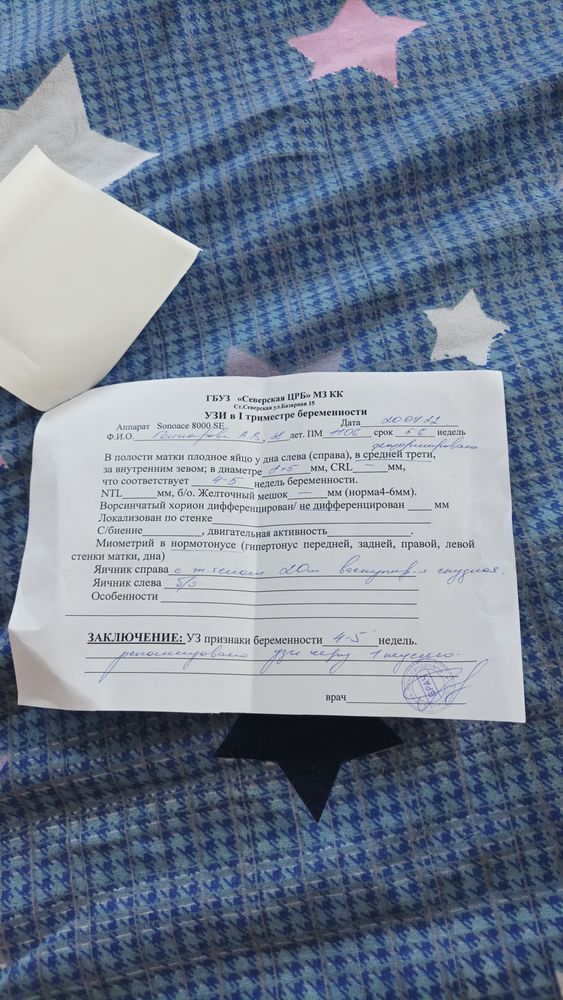

Девочки может было у кого так и всё кончилось благополучно, я сегодня пошла на УЗИ срок 5.4 чтобы проверить что всё на месте,плодное яйцо увидели но узистка сказала что может быть замершая потому что деформировано оно, но есть шанс что выпрямится, контроль через неделю, у меня до этого беременность тоже была замершая ,очень боюсь повторения, к врачу только 2 августа. Есть шанс что всё будет хорошо?